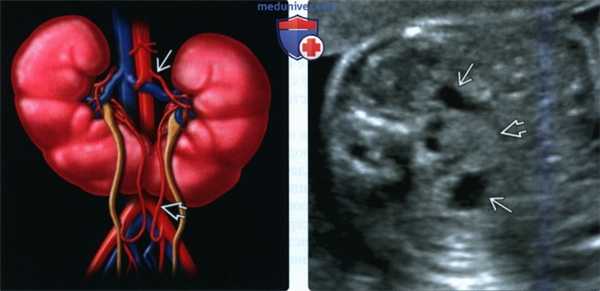

(Слева) Подковообразная почка. Нижние полюсы почек медиально отклонены, по срединной линии - перешеек. Питающие артерии, как правило, отходят от аорты или подвздошных артерий.

(Справа) Переднемедиальная ориентация лоханок может указывать на подковообразную почку. Тщательное сканирование по срединной линии позволяет даже во II триместре кпереди от аорты обнаружить паренхиматозную перемычку между почками.

• ЦДК:

о Источники кровоснабжения вариабельны:

- Происходят от аорты или подвздошных артерий

- Реже - от нижней брыжеечной, срединной крестцовой или диафрагмальной артерии

о Венозный отток также варьирует

(Слева) Подковообразная почка может иметь вид объемного образования брюшной полости. Однако в паренхиме почки обнаруживаются гипоэхогенные пирамиды коркового вещества и более эхогенная кора. Лоханки подтверждают предположение, что в поле зрения на самом деле подковообразная почка.

(Справа) Другой случай. ЦДК. Патологическая извилистость почечных артерий связана с объемным воздействием со стороны перешейка слившихся почек.